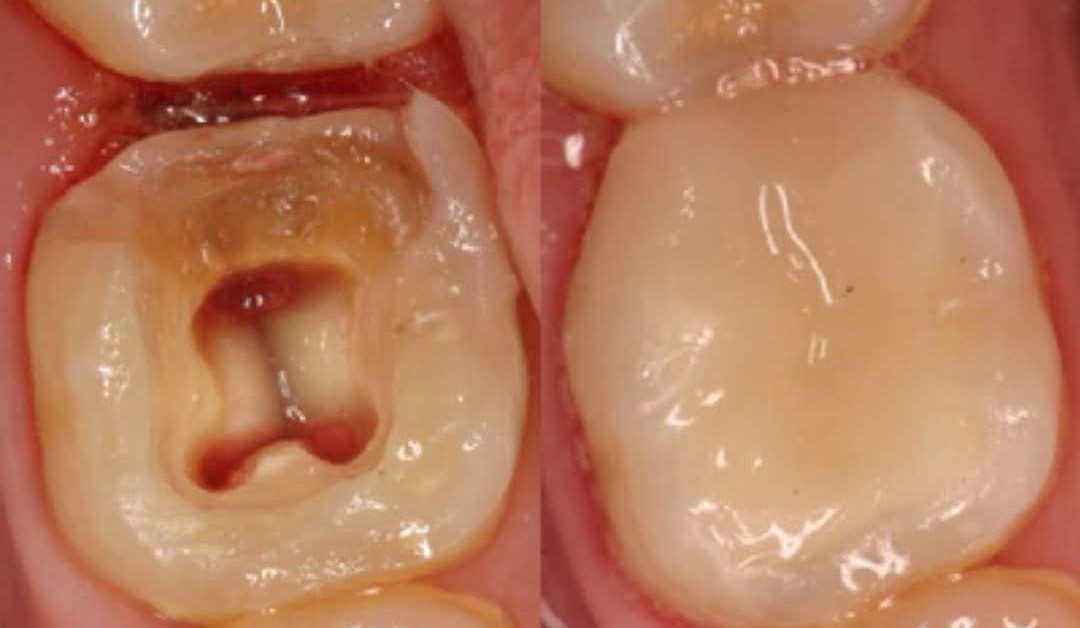

Реставративната стоматологија, пак, се надоврзува како уметност на враќање. Со користење на најсовремени материјали и технологии, се реконструираат оштетените или изгубените заби – без компромис во однос на природниот изглед, функцијата или удобноста. Без разлика дали станува збор за пломби, инлеи, коронки, мостови или импланти, секој реставративен зафат е прецизно дизајниран да се вклопи во хармонијата на вашата насмевка.